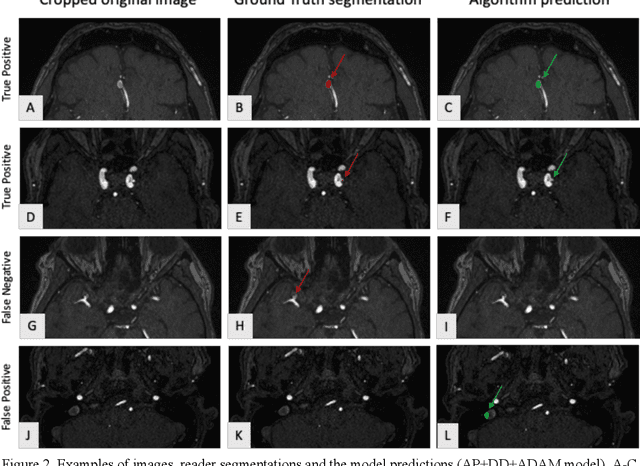

Abstract:Purpose: To develop an open-source nnU-Net-based AI model for combined detection and segmentation of unruptured intracranial aneurysms (UICA) in 3D TOF-MRI, and compare models trained on datasets with aneurysm-like differential diagnoses. Methods: This retrospective study (2020-2023) included 385 anonymized 3D TOF-MRI images from 364 patients (mean age 59 years, 60% female) at multiple centers plus 113 subjects from the ADAM challenge. Images featured untreated or possible UICAs and differential diagnoses. Four distinct training datasets were created, and the nnU-Net framework was used for model development. Performance was assessed on a separate test set using sensitivity and False Positive (FP)/case rate for detection, and DICE score and NSD (Normalized Surface Distance) with a 0.5mm threshold for segmentation. Statistical analysis included chi-square, Mann-Whitney-U, and Kruskal-Wallis tests, with significance set at p < 0.05. Results: Models achieved overall sensitivity between 82% and 85% and a FP/case rate of 0.20 to 0.31, with no significant differences (p = 0.90 and p = 0.16). The primary model showed 85% sensitivity and 0.23 FP/case rate, outperforming the ADAM-challenge winner (61%) and a nnU-Net trained on ADAM data (51%) in sensitivity (p < 0.05). It achieved a mean DICE score of 0.73 and an NSD of 0.84 for correctly detected UICA. Conclusions: Our open-source, nnU-Net-based AI model (available at 10.5281/zenodo.13386859) demonstrates high sensitivity, low false positive rates, and consistent segmentation accuracy for UICA detection and segmentation in 3D TOF-MRI, suggesting its potential to improve clinical diagnosis and for monitoring of UICA.